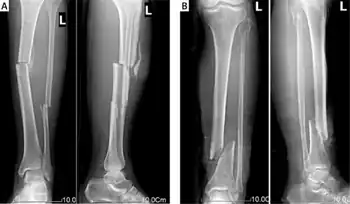

X-ray film of typical cases with open tibia and fibula fracture.

A tib-fib fracture is a fracture of both the tibia and fibula of the same leg in the same incident. Since the fibula is smaller and weaker than the tibia, a force strong enough to fracture the tibia often fractures the fibula as well. Types include: